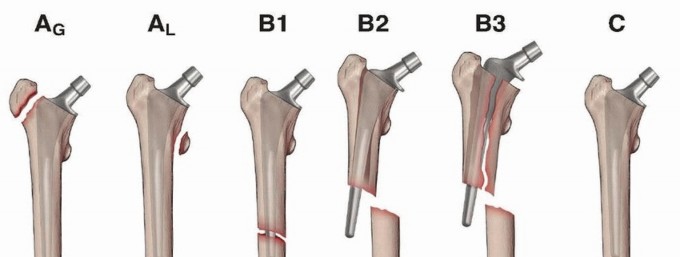

DEFINITION Periprosthetic fractures about a total hip arthroplasty are fractures which occur in the femur or …